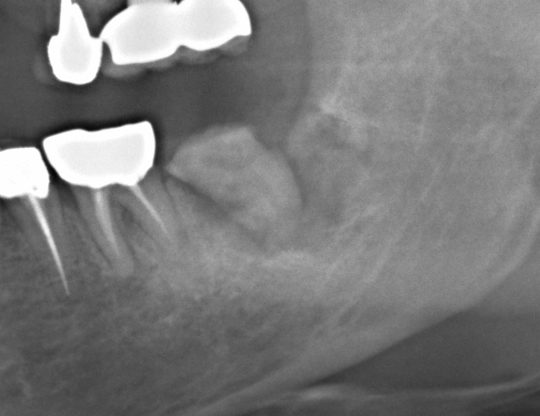

第2大臼歯が破折しており保存不能の状態です

奥に埋伏していた親知らずを同時に抜歯して、移植固定を行いました